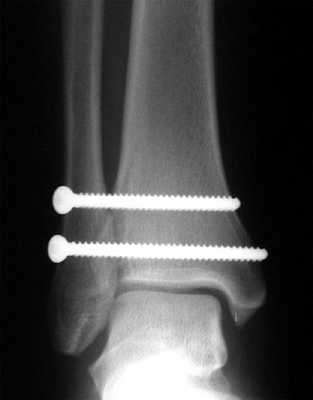

При детальном изучении снимков определяется увеличение межберцовой щели до 7,5 мм, уменьшения зоны перекрытия большеберцовой и малоберцовой костей до 5 мм, отсутствие на стороне поражения перекрытия тени таранной кости и малоберцовой кости.

На рентгенограмме костей правого и левого голеностопных суставов в прямой проекциии, снимки стоя - справа определяются признаки повреждения дистального межберцового синдесмоза - степень взаимного перекрытия берцовых костей 5мм (в норме больше 6мм) увеличенное большеберцовое - малоберцовое пространство - 7.5мм (в норме до 6мм).

При выполнении стресс рентгенограмм определяется выраженная латеральная нестабильность голеностопного сустава.

На рентгенограммах видно что после удаления позиционного винта взаимоотношения большеберцовой и малоберцовой костей остаётся прежним, что свидетельствует в пользу того что лечение прошло успешно.